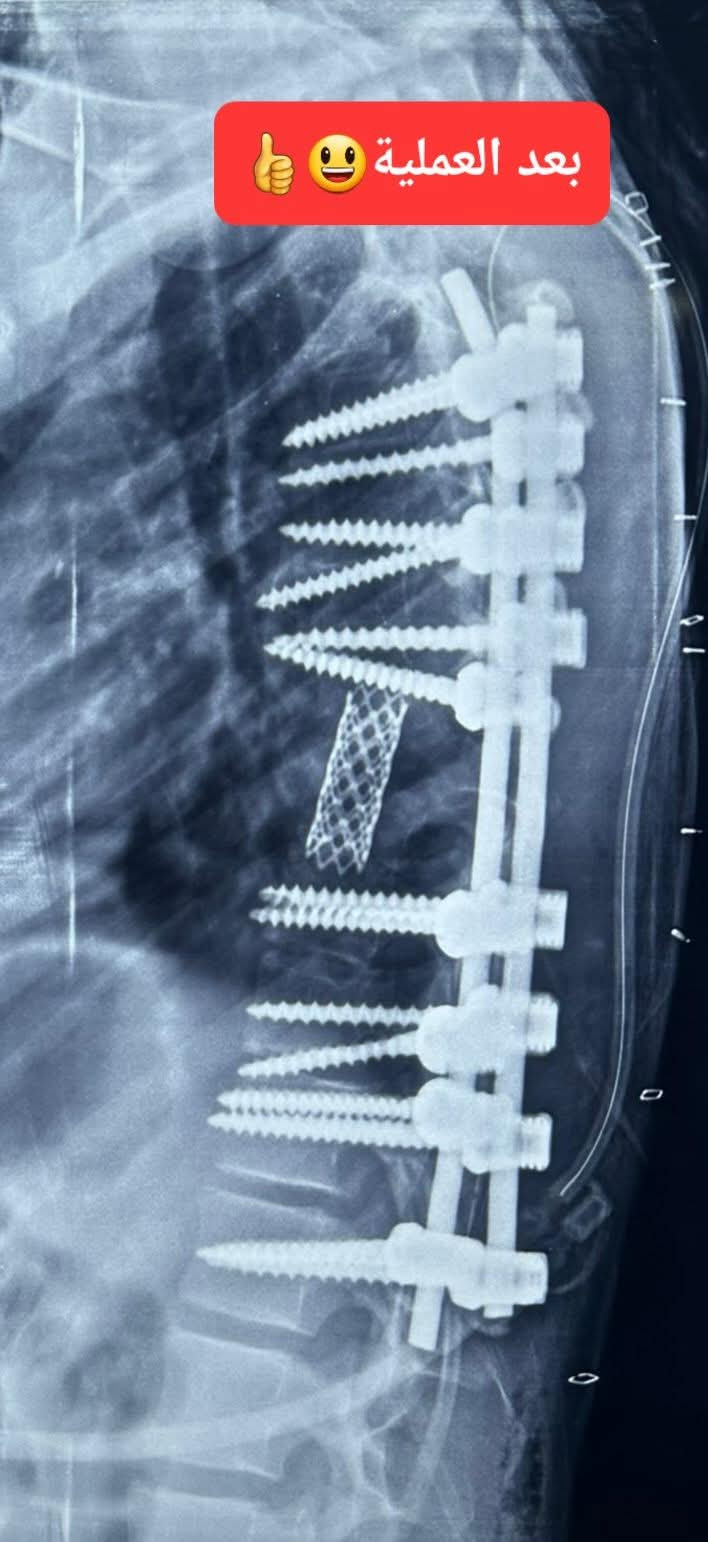

العملية شملت تحرير الحبل الشوكي، واستئصال الفقرة المشوّهة مع أجزاء من الفقرتين السابعة والتاسعة، وزراعة فقرة صناعية، إلى جانب تثبيت العمود الفقري بواسطة 18 مسماراً طبياً. كما تميّز التدخل بتصحيح الاعوجاجات المتعددة وإعادة التوازن للعمود الفقري بدرجة قريبة من الوضع الطبيعي.

وأوضح التركي أنه وبعد تشخيص دقيق ودراسة مستفيضة للحالة، قمت - بعون الله وتوفيه - ومعي الفريق الجراحي بعمل العملية النوعية والتي شملت تعديل وتصحيح اعوجاج العمود الفقري المتعدد والمعقد، وتحرير الحبل الشوكي، واستئصال الفقرة المشوّهة مع أجزاء من الفقرتين السابعة والتاسعة، وزراعة فقرة صناعية، وتثبيت العمود الفقري وتعديله بواسطة 18 مسماراً طبياً.

وقد تكللت العملية بالنجاح التام، إذ تمكنت الطفلة من الحركة والمشي في اليوم الثاني بعد الجراحة، الأمر الذي أنهى معاناتها وفتح أمامها باب حياة جديدة.